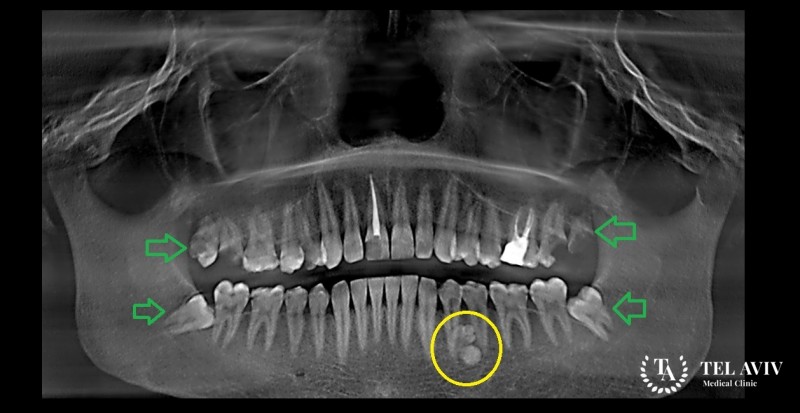

Основным способом обследования при подозрении на одонтому считается рентгенография. Также, для исключения злокачественной патологии в Tel Aviv Medical Clinic применяется гистологическое исследование. В израильскую клинику обращаются люди со всего мира в надежде на получение адекватной медицинской помощи. Благодаря использованию современного оборудования, наши высококвалифицированные специалисты добиваются максимальной точности результатов диагностики, определяя тип новообразования, его степень развития, сопутствующие нарушения. Лечение назначается по индивидуальным показателям, возрасту и состоянию пациента, особенностей течения патологии.